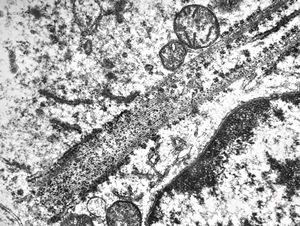

M,18y. | tubuloreticular complex in lymphocyte - unclassified hematologic disorder